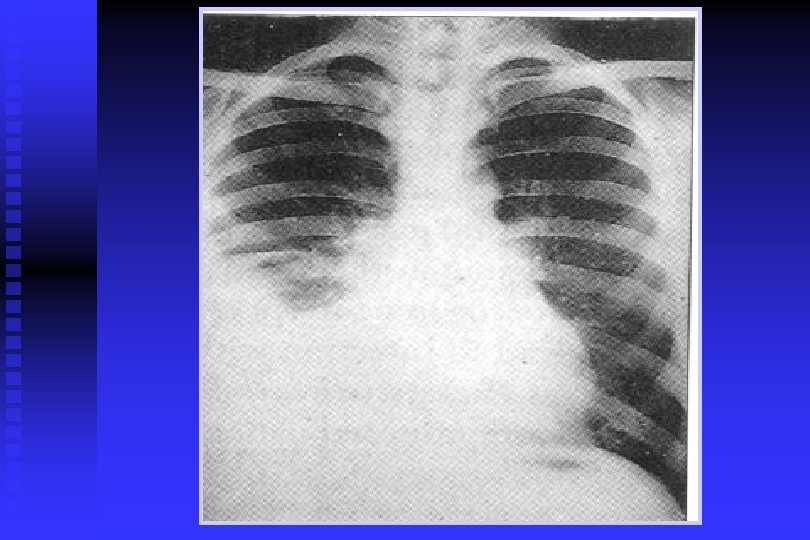

Cancer Pulmonar

DIAGNOSTICO DE CANCER PULMONAR RADIOGRAFIA DE TORAX: Permite descubrir CP en asintomáticos en 67 -82% y de estos el 24% tiene citología de esputo anormal. TOMOGRAFIA DE TORAX: Sensibilidad del 85% para CP y una especificidad del 95%. Per– mite descartar causas benignas de nódulos pulmonares con uni – dades Hounsfield >175= benigno; adenopatías <1 cm= benignos; 1 -2 cm= Indeterminado, >2 cm= positivo. Permite conocer actividad metastásica, y para estadificación (S= 73% y E= 80%).